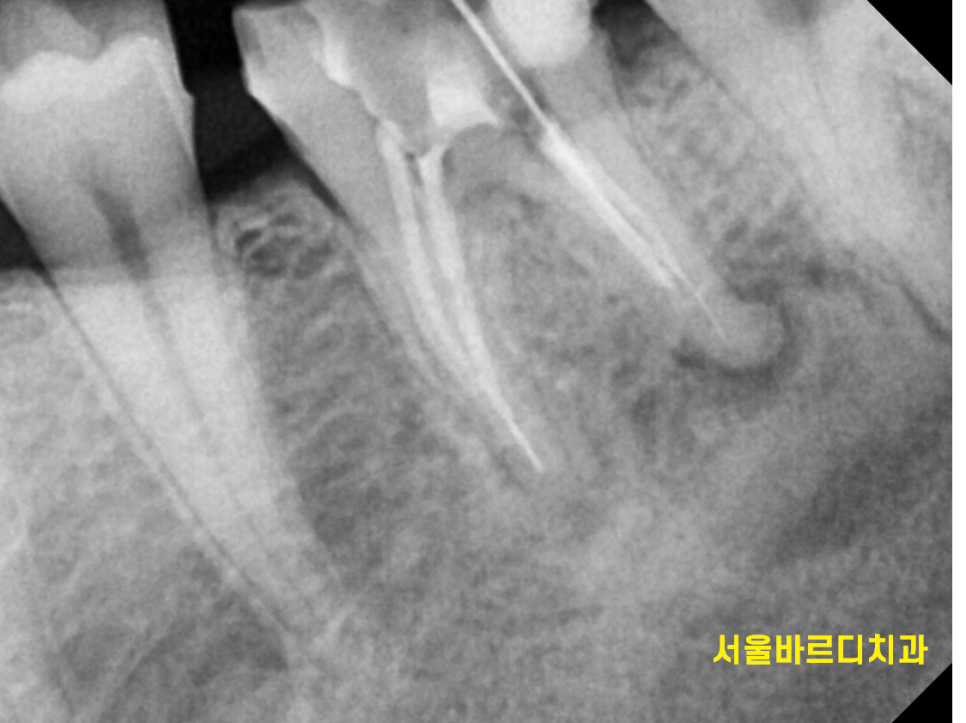

재신경치료는 기존 신경치료가 실패한 경우에

치아를 살리기 위해 다시 감염 부위를 제거하고 치료하는 과정입니다.

기존 치료물을 제거하고 감염된 부위를 세밀하게 소독하며,

기존 치료에서 발견하지 못했던 추가적인 감염 경로를 찾아내는 것이 핵심이에요!!

염증이 어느정도 해소될 때까지 소독도 해야하고

염증의 근본 원인을 해결해야하기 때문에

몇번씩 오셔야한답니다.

240117 기존 보철도 제거하고 치료해야하기도 하죠...